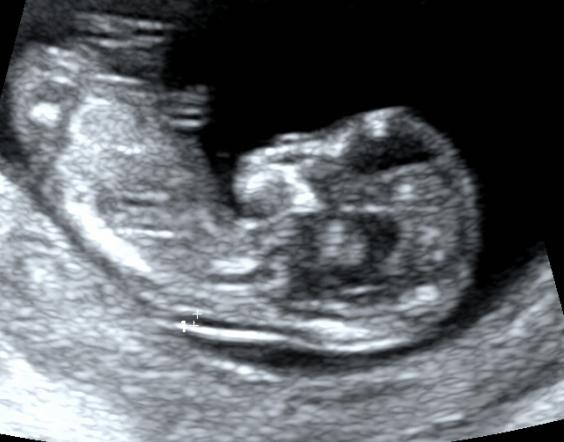

当然,这个时期我们除了重点观察TA的肢体以外,此时需要重点关注NT。

NT测量一般在11-13+6周内进行。

此时测量彩具有参考意义,但测量NT完全看宝宝的心情。

因为TA 有时候真的很不给面子。。。

还有倒立的

还有直接给个背影的。。。。